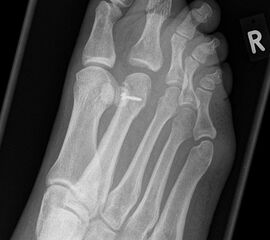

Fuß seitlich mit Belastung

Positionierung:

• Der Patient steht auf beiden Füßen mit gleichmäßiger Lastverteilung.

• Der zur Röntgen der Fuß wird längs des Films positioniert.

• Die Kassette steht senkrecht zum Boden, medial dem Fuß anliegend.

• Der Zentralstrahl wird von lateral nach medial zentriert auf das Kalkaneokuboidalgelenk knapp cranial der Os metatarsale V Basis ausgerichtet.

• Die Röntgenröhre steht 0° horizontal.

Kennzeichen des Röntgenbildes:

• Standardabbildung des Fußes zusammen mit der belasteten d.-p. Aufnahme und der unbelasteten 45° Pronationsaufnahme.

• Überblick über die Fußanatomie und Fußstatik.

• Die seitliche Aufnahme liefert Informationen zur Stabilität des Längsgewölbe und zu den Achsen von Talus, Kalkaneus und Metatarsale I.

• Die Aufnahme wird eingesetzt zur Darstellung von freien Gelenkkörpern sowie knöchernen Veränderungen am Achillessehnenansatz oder der Plantarfaszie.

Besondere Bemerkungen zum Beispielbild:

• Schwere Hallux valgus Deformität.

• Die Sesambeine sind luxiert, ebenso das Großzehengrundgelenk. Luxation des Metatarsophalangealgelenks II.

• Degenerative Veränderungen der tarsometatarsalen (TMT) Gelenkreihe, betont TMT II und III.